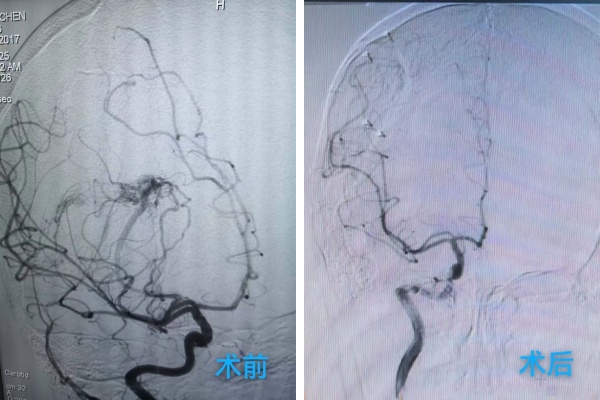

庞克军主任医师紧急启用神经外科绿色通道,导管室协助,由神经外科医师紧急行脑血管造影术检查,检查快速且准确,可以看见小雨颅内是有动脉畸形,并且是2处!

我院神经外科团队学科讨论后一致认为小雨必须立即进行开颅手术,清除血肿、处理畸形血管团,以解除对脑组织的压迫,为患儿争取最大的康复希望。

在麻醉科协助下,手术显微镜下动静脉畸形(AVM)不是单纯的肿瘤,而是一团异常缠绕的血管球,其内血流动力学极其紊乱,血管壁脆弱,极易在分离过程中破裂出血。然而小雨动脉畸形病灶位于“功能区”周围,意味着这团畸形的血管就是“镶嵌”在大脑控制对侧肢体运动、感觉甚至语言的核心区域,任何轻微的牵拉、电凝或血供干扰,都可能导致永久性的功能损伤,更危险的是儿童的脑组织尚在发育中,比成人更加娇嫩,对手术牵拉、缺血缺氧的耐受能力更差。庞克军主任医师以精湛的技术和极大的耐心,小心翼翼地清除了压迫脑组织的血肿,并以微米级的精度进行操作,沿着AVM与正常脑组织之间的“胶质带”进行分离,力求完好无损地剥离畸形团。整台手术操作精准、流畅,成功拆除了埋藏在小雨脑内的“炸弹”。